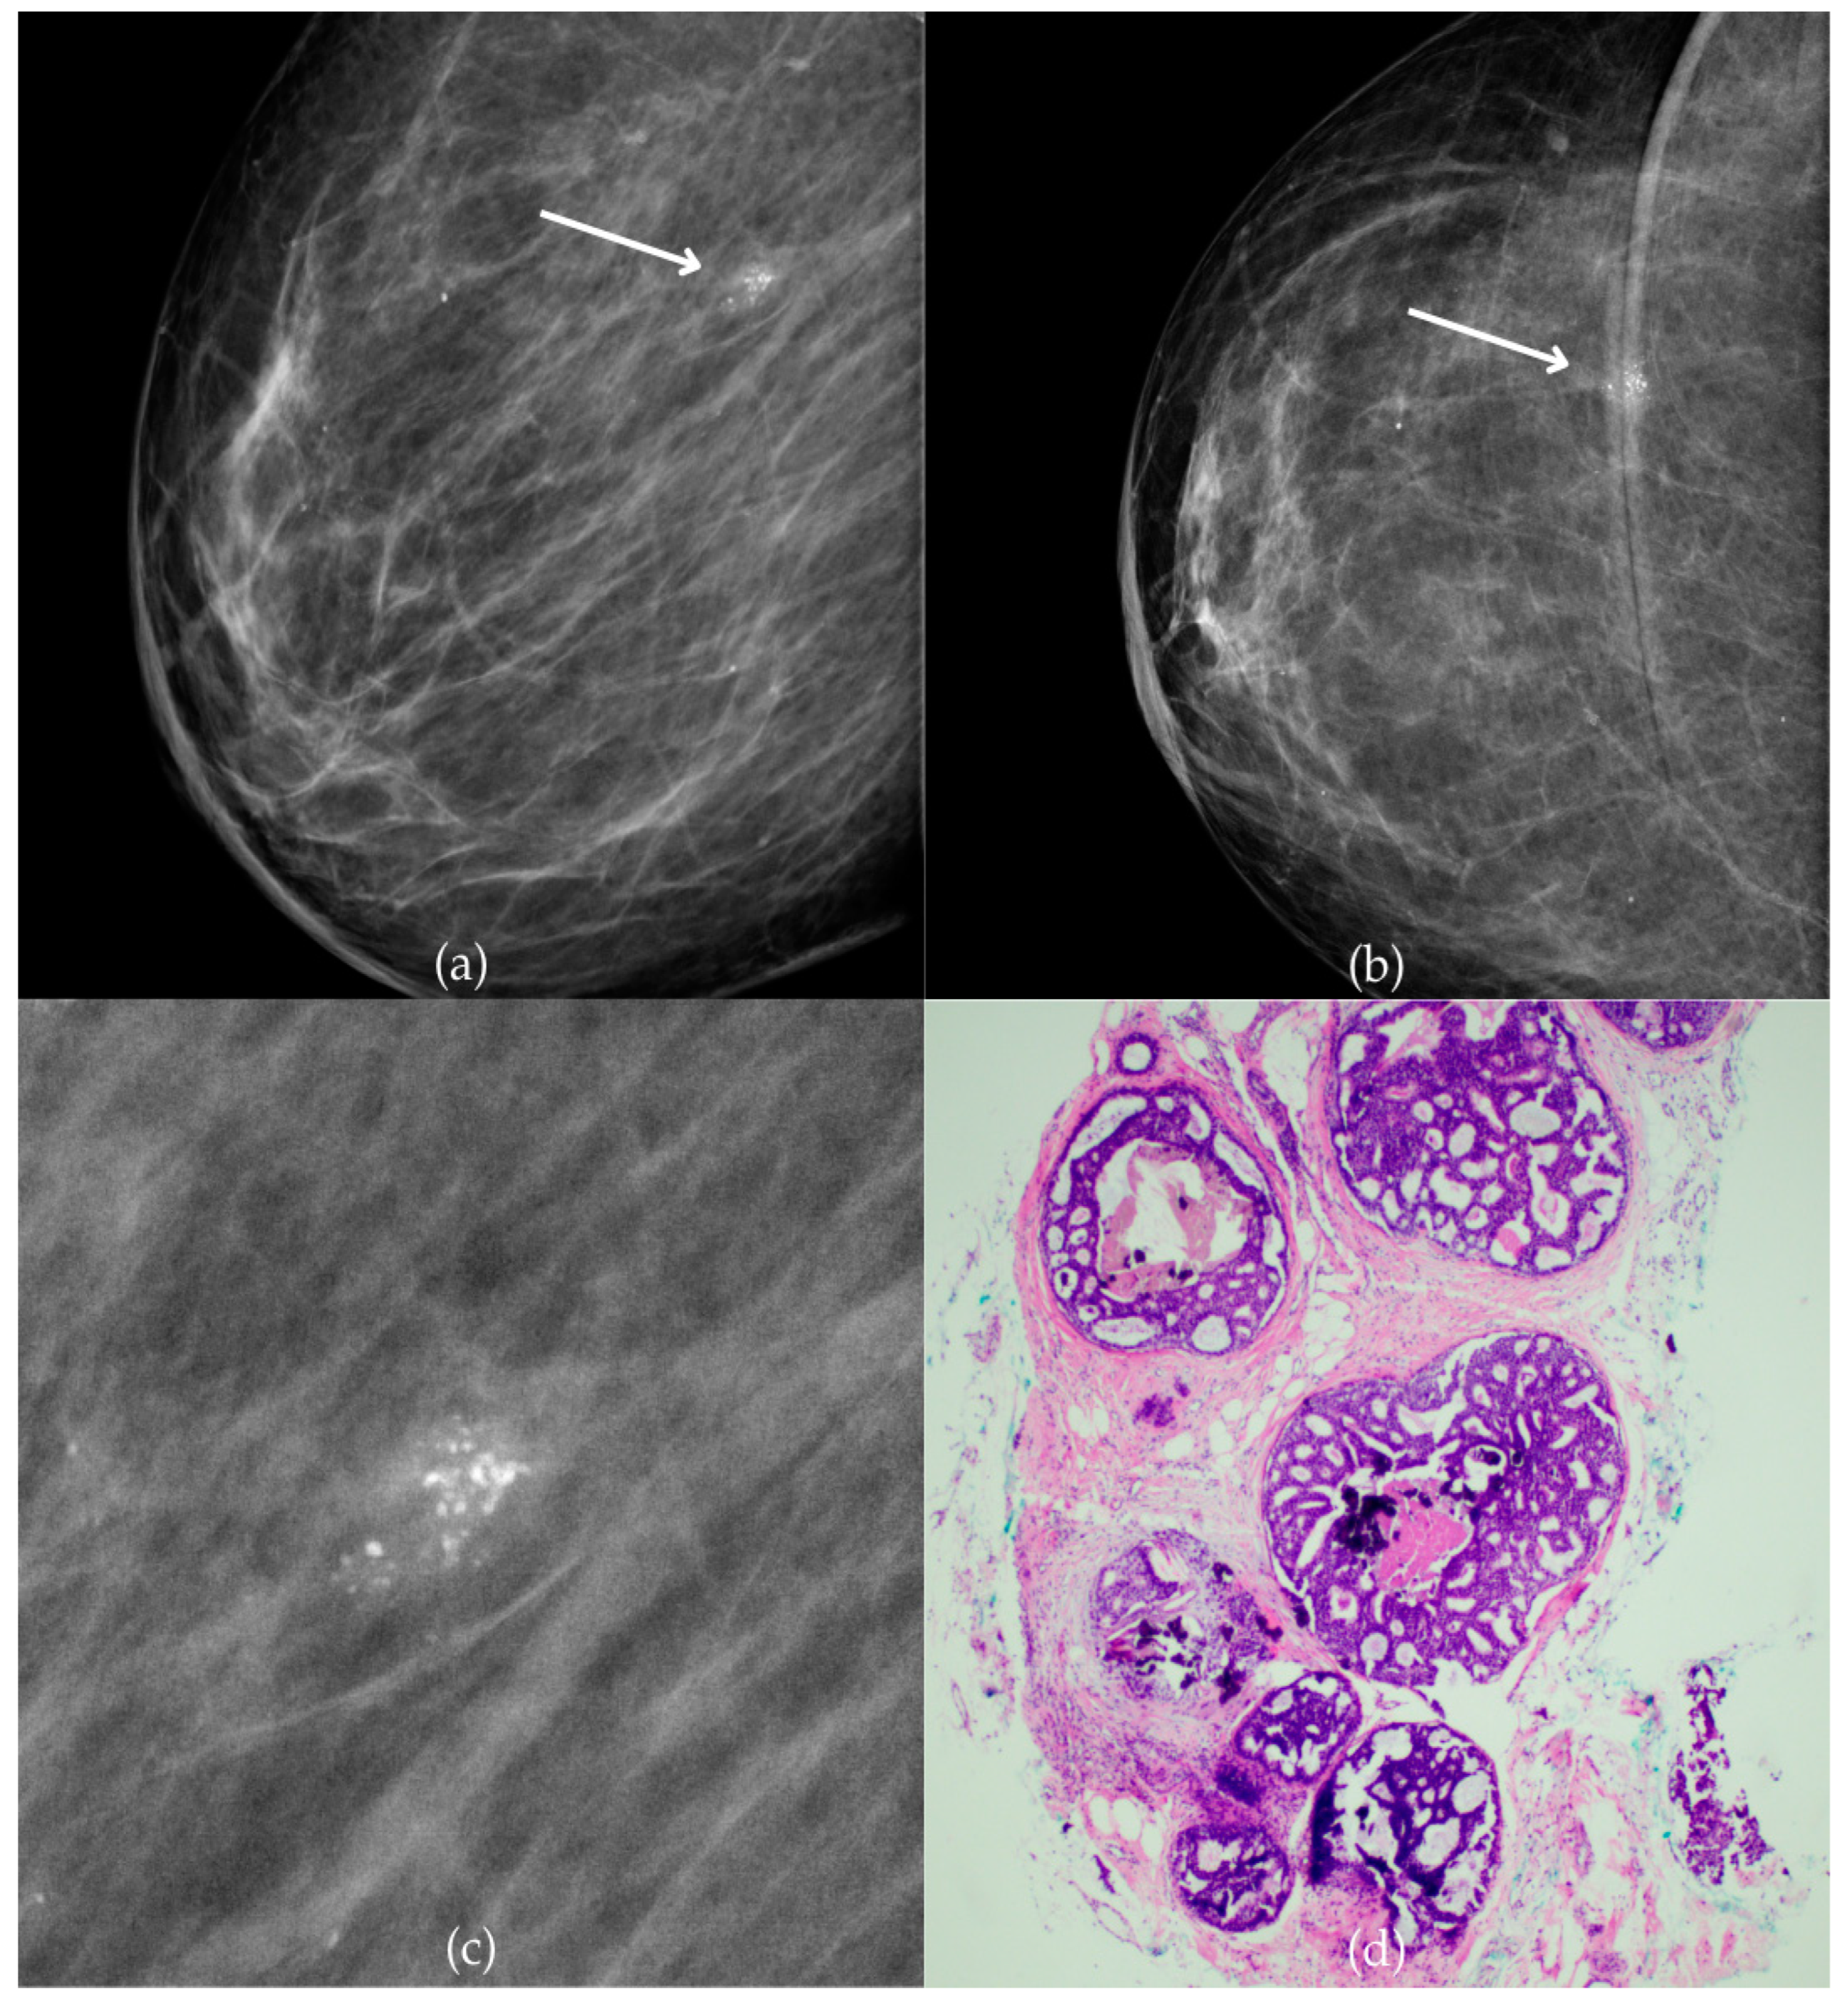

Figure 6 presents mammographic and histopathological images of a 49-year-old patient. The mammogram of the patient’s right breast shows amorphous calcifications of regional distribution in the outer quadrants border, corresponding to a BI-RADS 3 finding. Tissue analysis obtained through biopsy confirmed the presence of DCIS (category B5a). The patient underwent a mastectomy, and postoperative pathology confirmed the diagnosis of carcinoma in situ. One year after diagnosis, the follow-up MRI and US were reported as BI-RADS 2, confirming the absence of malignancy.

Figure 6.

Ductal carcinoma in situ (DCIS). (a) Mediolateral oblique (MLO) view; (b) craniocaudal (CC) view of the right breast showing amorphous calcifications of regional distribution (marked with arrows) in the outer quadrants border. (c) Magnified mammographic image of amorphous calcifications of regional distribution. (d) The histopathological image of the biopsy sample shows the characteristic features of DCIS (HE staining; 100× magnification).